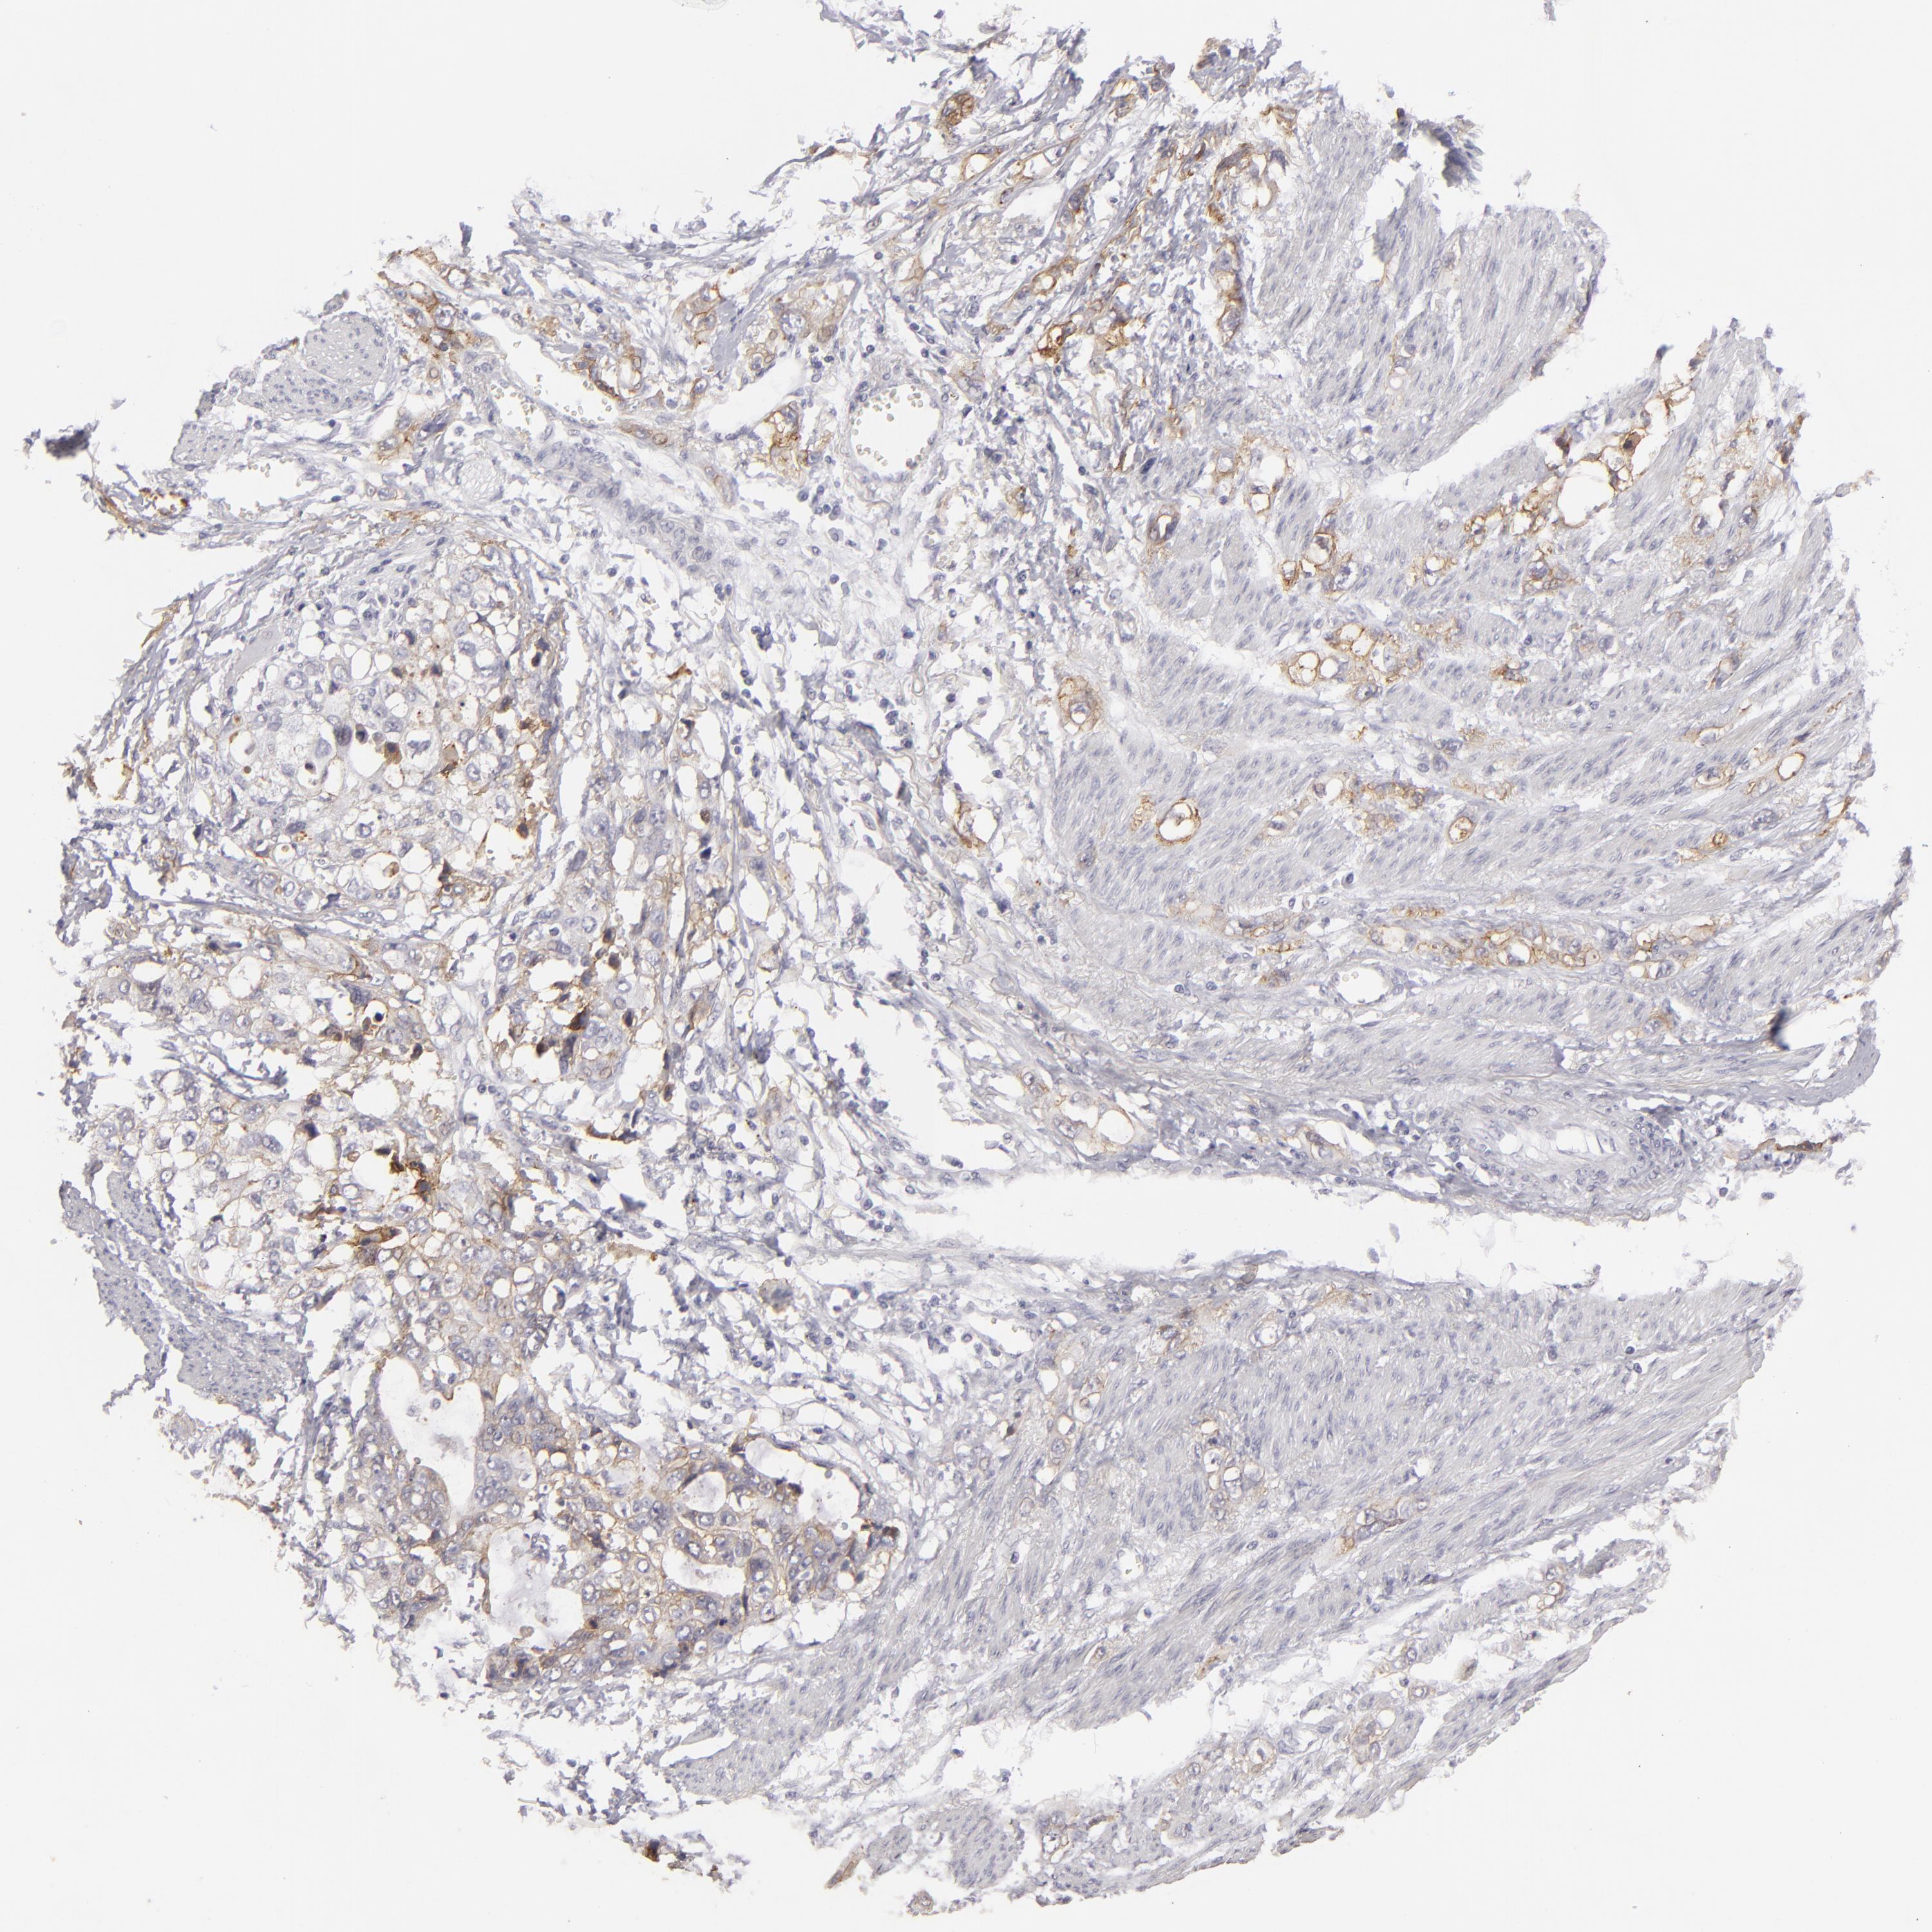

STOMACH CANCER - Protein expressioni

A mouse-over function shows sample information and annotation data. Click on an image to view it in a full screen mode. Samples can be filtered based on level of antibody staining by selecting one or several of the following categories: high, medium, low and not detected. The assay and annotation is described here.

Note that samples used for immunohistochemistry by the Human Protein Atlas do not correspond to samples in the TCGA dataset.

Antibody stainingi

Antibody staining in the annotated cell types in the current human tissue is reported as not detected, low, medium, or high, based on conventional immunohistochemistry profiling in selected tissues. This score is based on the combination of the staining intensity and fraction of stained cells.

Each image is clickable and will lead to virtual microscopy that enables deeper exploration of all samples and also displays staining intensity scores, fraction scores and subcellular localization as well as patient and tissue information for each sample.

Antibody HPA032047

Antibody CAB002139

Staining

High

Medium

Low

Not detected

Intensity

Strong

Moderate

Weak

Negative

Quantity

>75%

75%-25%

<25%

None

Location

Nuclear

Cytoplasmic/membranous

Cytoplasmic/membranous,nuclear

Adenocarcinoma, NOS